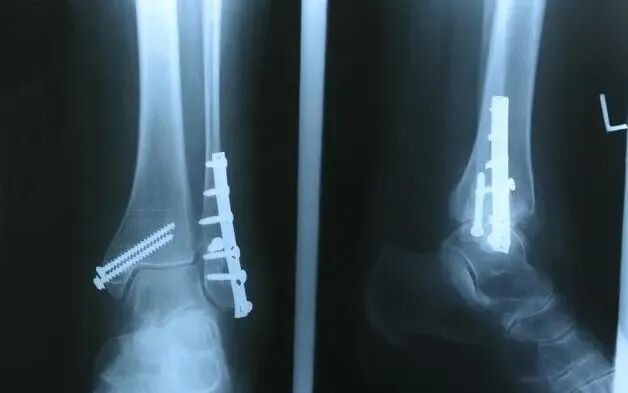

骨折是指在相关因素的影响下,对人体骨骼的完整性和连接性造成破坏,从而引起相关位置的肿胀和疼痛,影响活动和生活。

随着年龄的增长,骨质疏松症逐渐出现,对外界的适应性降低,轻微的外力引起骨折;此外,长期从事某种劳动,或姿势不正确,导致身体某一部位严重劳损,也容易诱发骨折。有些疾病会影响体内钙的吸收,引起骨质疏松,或引起骨质过度破坏,也会引起骨折。常见病有内科疾病.软骨发育不良.骨肿瘤等。骨折后愈合时间的长短,骨折的位置.骨裂的原因.骨折的严重程度与治疗方法密切相关。此外,还有一些个别差异。